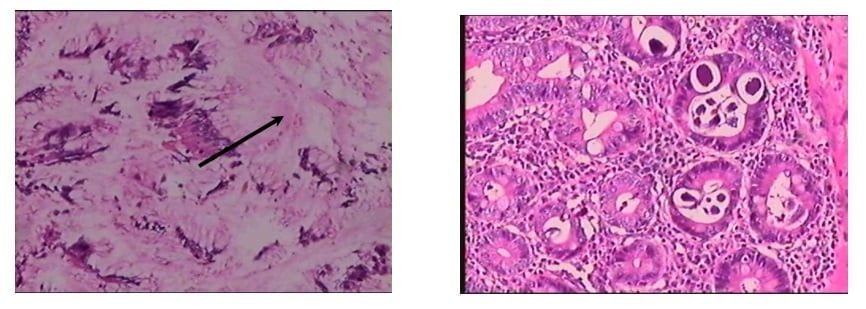

Hình ảnh giun lươn (mũi tên) trong ruột non và hình ảnh viêm loét dạ dày

ẢNH: BVCC